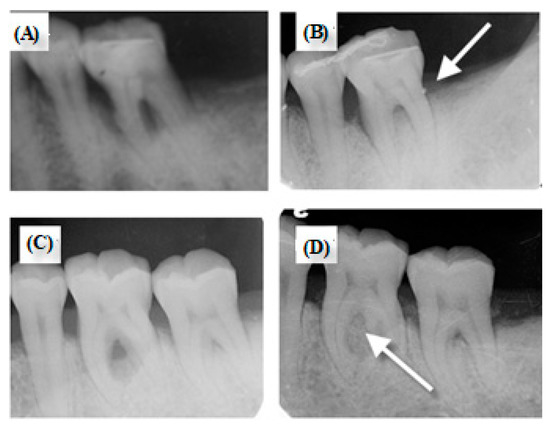

2.4. Clinical Trial

3.4. Clinical Trial